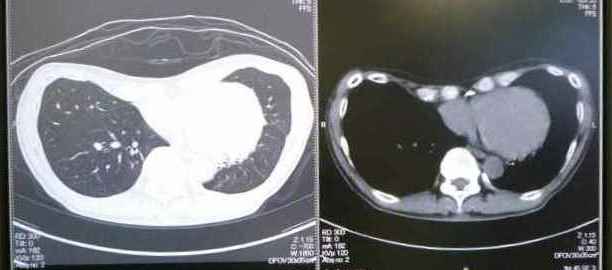

09月21日(火) 気管支から雑音